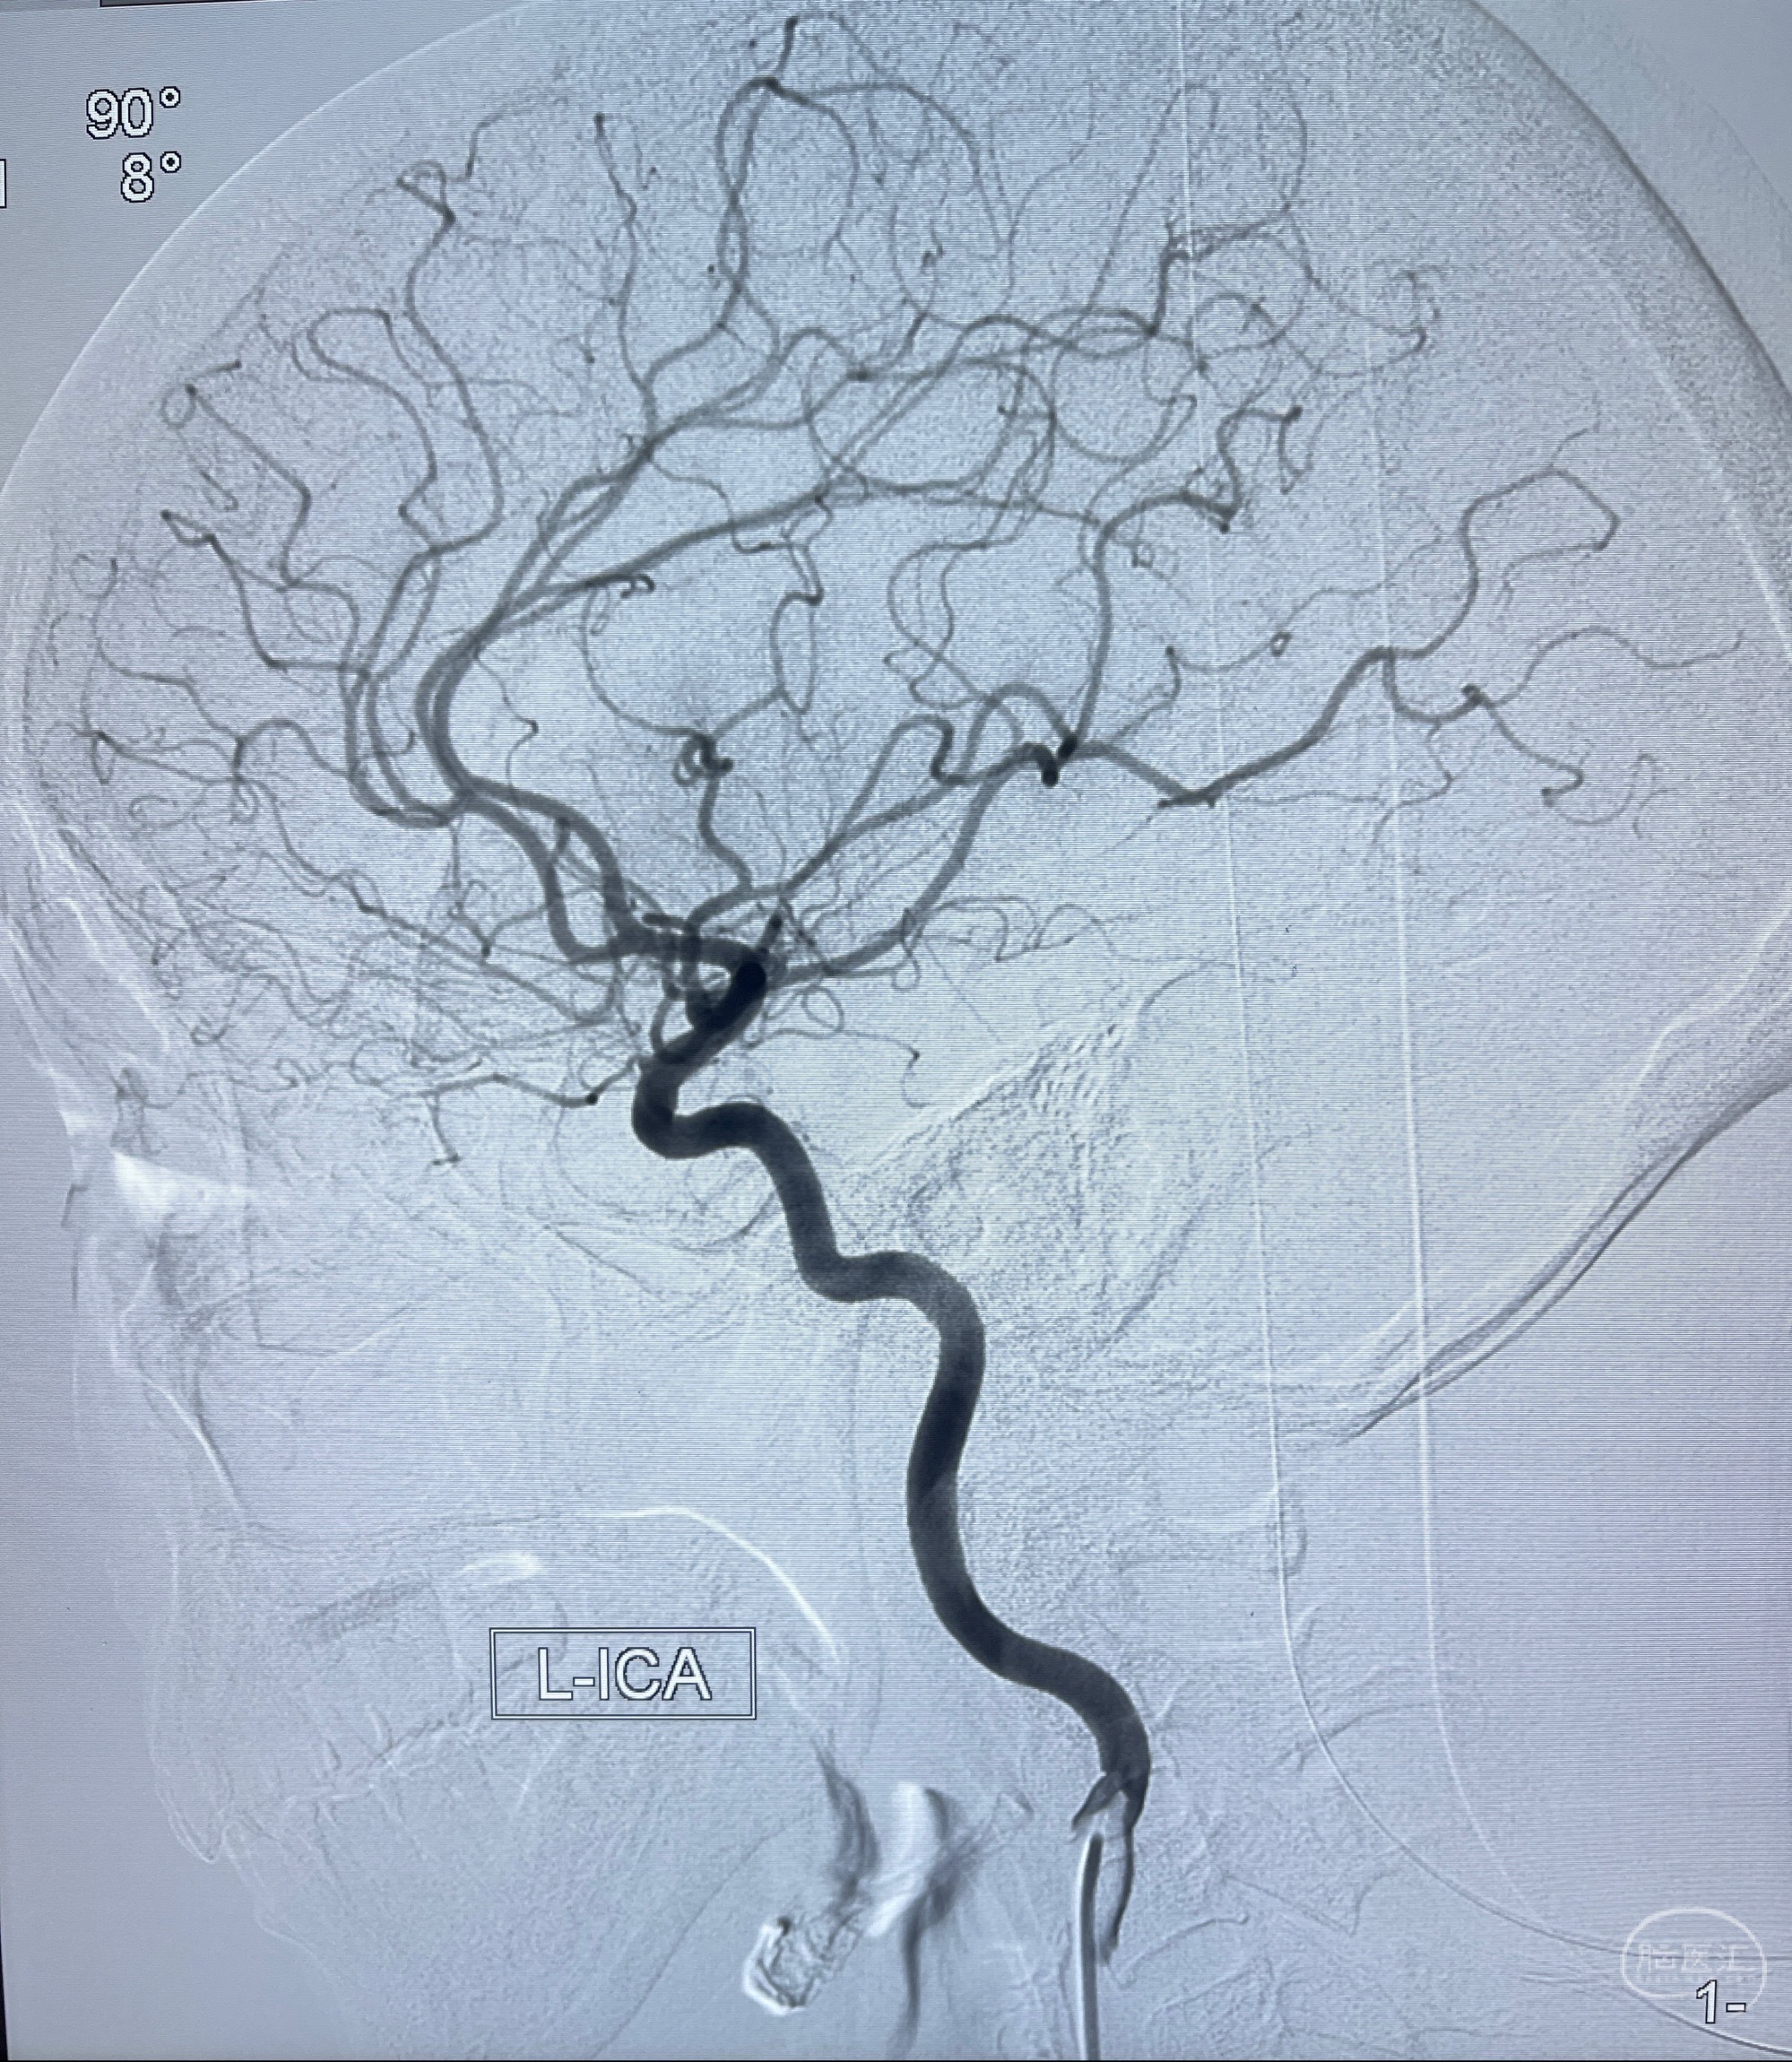

2023-08-14DSA:

左侧大脑中动脉动脉瘤,约2.6-2.8-3.4-2mm大小(瘤颈部、瘤体部、瘤高)

1.左侧大脑中动脉动脉瘤,约2.6-2.8-3.4-2mm大小(瘤颈部、瘤体部、瘤高)

2.外科手术夹闭or介入支架辅助栓塞